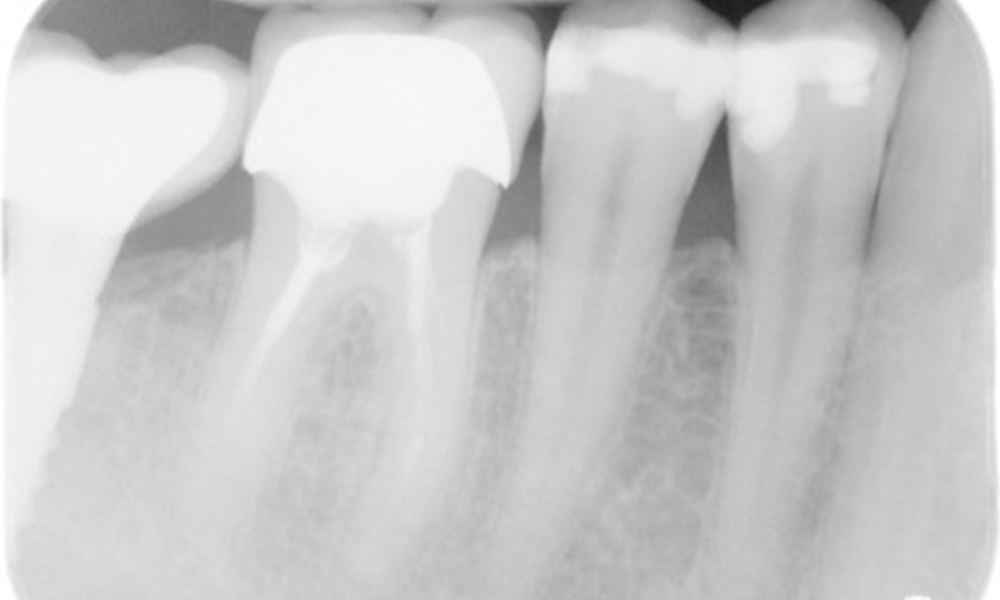

Röntgenaufnahme zeigt Knochenabbau

Die Röntgenaufnahme zeigt den Knochenabbau.

Zahnfilme (bzw. Bissflügelröntgen)

Zahnfilme (bzw. Bissflügelröntgen) aufgenommen am: 18.02.2021